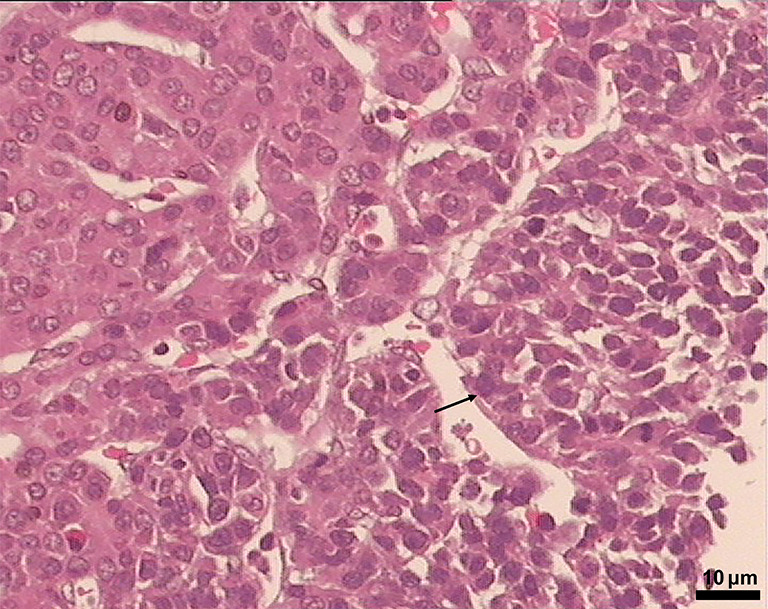

Background: Beckwith-Wiedemann syndrome (BWS) is a genetic disorder characterized by various clinical features. The purpose of this study was to investigate the molecular diagnostic and clinical features of BWS in Chinese pediatric patients.

Methods: This retrospective study reviewed the clinical data of 24 pediatric patients diagnosed with BWS at the Guangzhou Women and Children's Medical Center, Guangzhou Medical University from 2014 to 2024. To assess genetic abnormalities, molecular analysis was performed using array comparative genomic hybridization (Array-CGH) as well as methylation-specific multiplex ligation-dependent probe amplification (MS-MLPA).

Results: With a range of fetal period to four years, the median age at diagnosis was nine months. Cardinal features were macroglossia (95.8%), lateralized overgrowth (54.2%), and omphalocele (25%). Suggestive features included transient hypoglycemia (20.8%), hepatomegaly or nephromegaly (8.3%), and facial port-wine stain or ear-lobe creases (8.3%). Molecular analysis revealed that 57.9% of patients had methylation abnormalities in the imprinting control region 2 (IC2), while 5.3% had abnormalities in imprinting control region 1 (IC1), and 36.8% diagnosed with uniparental disomy (UPD). One patient also exhibited a rare homozygous mutation in the DUOX2 gene and a heterozygous mutation in the LDLR gene.

Conclusions: This study investigates the significance of early genetic testing in the clinical and molecular features of pediatric BWS demonstrating that MLPA exhibits its higher sensitivity and specificity for genetic testing in these patients. Furthermore, the findings identified a high prevalence of UPD in the southern Chinese population and highlighted the diagnostic role of chromosomal microarray analysis (CMA) in detecting UPD-related phenotypes in patients with BWS.